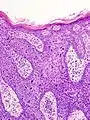

Maladie de Bowen

La maladie de Bowen est un carcinome épidermoïde (ou spinocellulaire) intra-épidermique (carcinome in situ), favorisé par le soleil et l'arsenic. Elle peut toucher la peau mais aussi les muqueuses[1]. Elle se présente sous la forme d'une lésion brun rougeâtre arrondie ou arciforme bien limitée dont la surface est un peu surélevée et squameuse[1]. Son diagnostic est histologique. Son évolution est très lente et la maladie présente un excellent pronostic de guérison. En revanche, en l'absence d'un diagnostic et d'un traitement approprié, elle évolue lentement mais sûrement vers un véritable carcinome épidermoïde invasif[1].